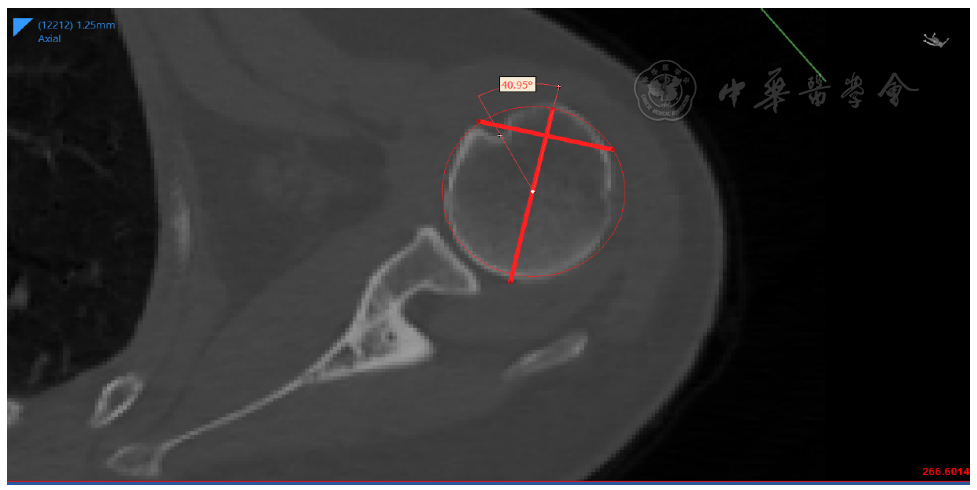

图1 结节间沟测量定位:O(肱骨头近似圆心)→Q(过大结节中点之切线)→L(⊥Q)→D(沟最低点)

图4 PIG定义为D点与参考线Q的夹角,使用Mimics软件进行测量注:PIG为结节间沟位置